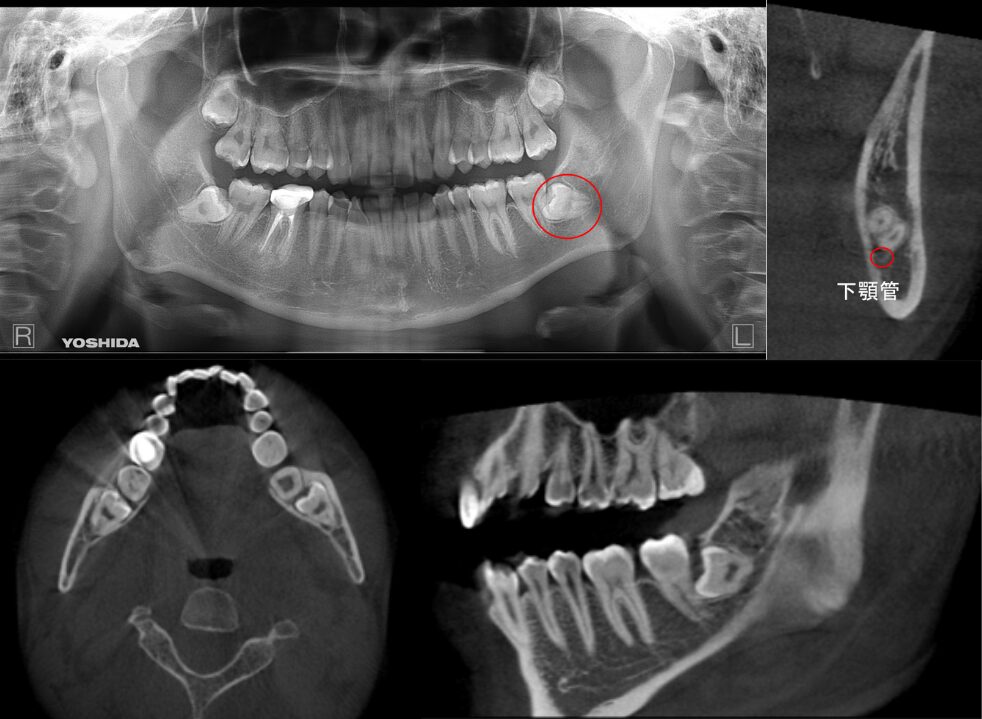

完全に骨に埋伏している症例

| 患者情報 | 24歳 男性 |

| 手術時間 | 30分 |

| 治療内容 | 親知らず抜歯 |

| グレゴリー分類 | クラスⅢ position B |